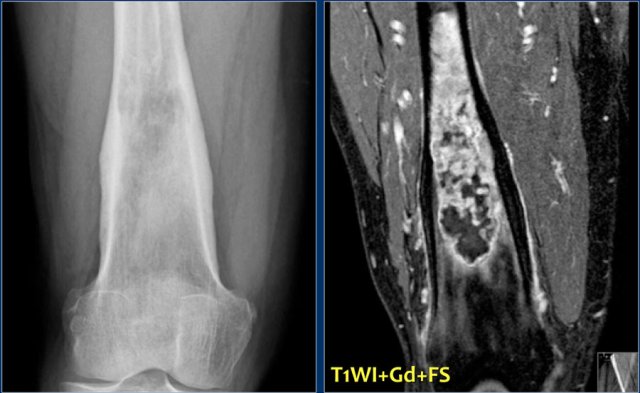

Here images of an osteosarcoma in the right femur.

It is barely visible within the bone, but an agressive periostitis is seen (arrow).

Continue with the MR-images.

The sagittal T1WI and Gd-enhanced T1W-image with fatsat show a large tumor mass infiltrating a large portion of the distal femur and extending through the cortex into the soft tissues.